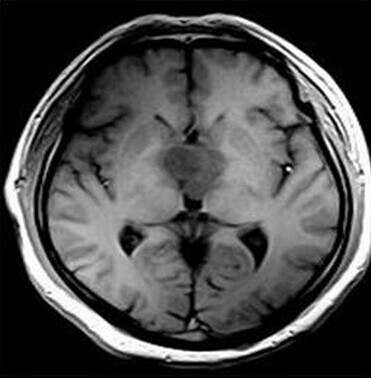

第三脑室脊索样胶质瘤

患者:男,50岁,记忆力下降1月余,双眼视力下降,反应减慢。

【正确答案】D 胶质瘤(第三脑室脊索样胶质瘤)

第三脑室脊索样胶质瘤的特征性表现是:

(1)见于成人,边界清楚,位于第三脑室前部;

(2)T1WI上为低信号,T2WI上呈明显高信号;

(3)增强后明显强化;

(4)肿块累及视交叉及下丘脑,但不浸润周围脑实质。